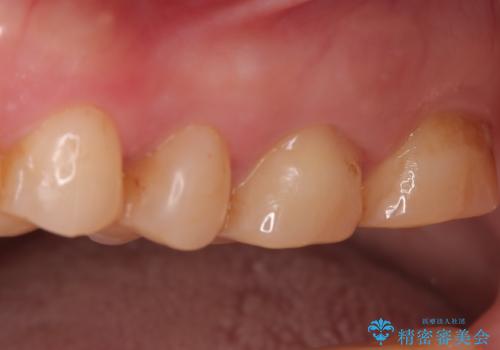

欠けやすい大きなプラスチック充填から、耐久性の高いセラミッククラウンへ

担当医 河口智英